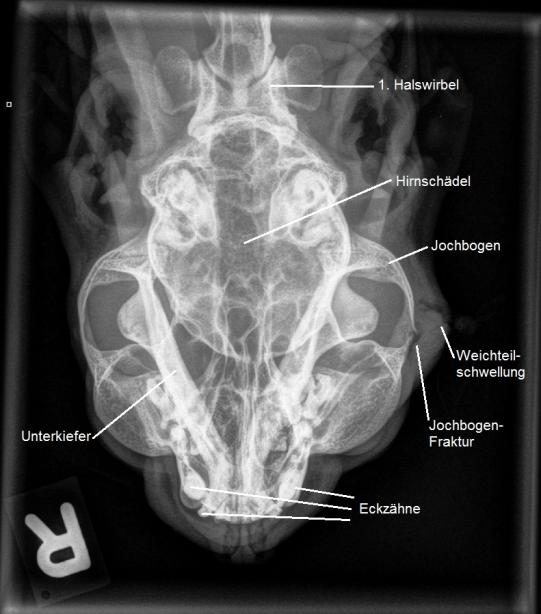

Seltsamerweise verheilt der Abszess so aber nicht innert etwa einer Woche - die Abszesshöhle füllt sich nach Entfernung der Drainage wieder mit Eiter. Eine zweite Narkose wird verabreicht und eine Röntgenaufnahme des Schädels angefertigt. Verblüfft stellen wir fest, dass die Katze, welche Timi gebissen hatte, nicht nur ein Loch in die Haut, sondern gleich auch noch einen Knochenbruch in den Jochbogen gebissen hatte!

Dass bei einer Bissverletzung auch gleich ein Knochen frakturiert wird, ist bei Katzen hingegen sehr unüblich. Bei Timi hat jedenfalls die Fremdkörperreaktion der abgesplitterten Knochenstückchen bewirkt, dass die Verletzung erst nach mehreren Anläufen erfolgreich zur Abheilung gebracht werden konnte.